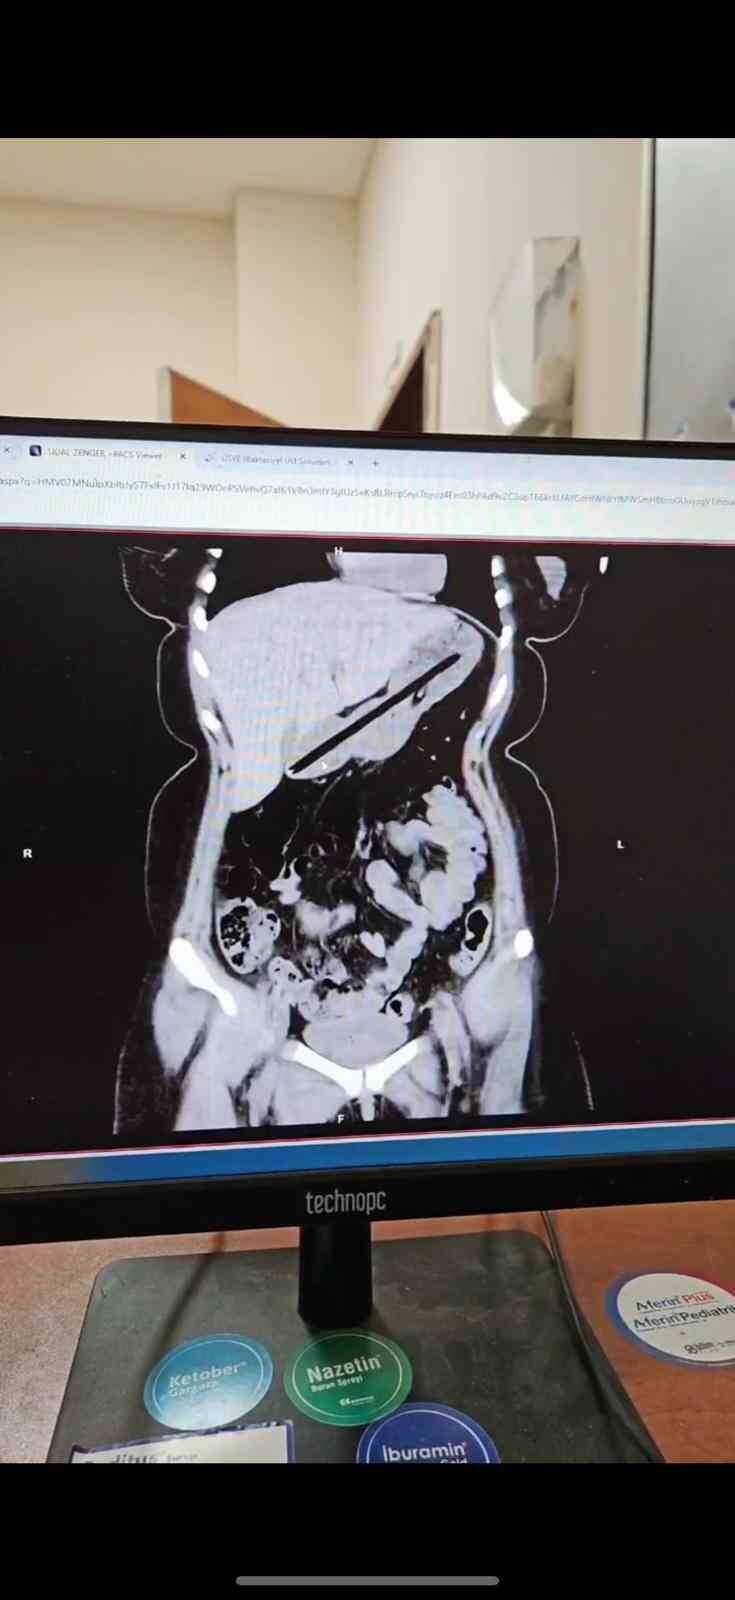

Ağrı’da Obsesif Kompulsif Bozukluk (OKB) rahatsızlığı bulunan 22 yaşındaki kadın, kalem yutma şikayetiyle hastaneye kaldırıldı. Ailesi tarafından Ağrı Eğitim ve Araştırma Hastanesi Acil Servisi’ne getirilen hastanın midesinde yabancı cisim tespit edildi. Genel Cerrahi ekibince ertesi gün gerçekleştirilen yaklaşık bir buçuk saat süren endoskopi operasyonuyla genç kadının midesinden biri kurşun, diğeri tükenmez olmak üzere iki kalem çıkarıldı. Başarıyla sonuçlanan operasyonun ardından hasta bir gün müşahede altında tutularak taburcu edildi.

Operasyonu gerçekleştiren Dr. Öğretim Üyesi Adem Aslan, ilk kez böyle bir vakayla karşılaştıklarını belirterek, “22 yaşındaki bayan hastamız kalem yutma şikayetiyle ilçe devlet hastanemize başvurmuştu. Tomografisinde midesinde yabancı cisim olduğu görüldü. Biz de tetkiklerimizde midesinde kalem olduğunu gözlemledik. Daha önce toplu iğne, kemik parçası gibi yabancı cisimlerle karşılaşıyorduk ama bu kadar uzun ve ince bir cisim ilk kez karşımıza çıktı. Midenin boşalması için bir gün bekledik ve ertesi gün yaptığımız endoskopide hastanın bir değil iki kalem yuttuğunu gördük. Yaklaşık bir buçuk saat süren işlemde kalemleri endoskopik yöntemle çıkardık. Hastamızın Obsesif Kompulsif Bozukluğu olduğu için ailesine yalnız bırakmamalarını ve bu tür cisimleri ortalıkta bulundurmamalarını tembih ettik. Bir gün müşahede altında tuttuktan sonra şifa ile taburcu ettik” dedi.